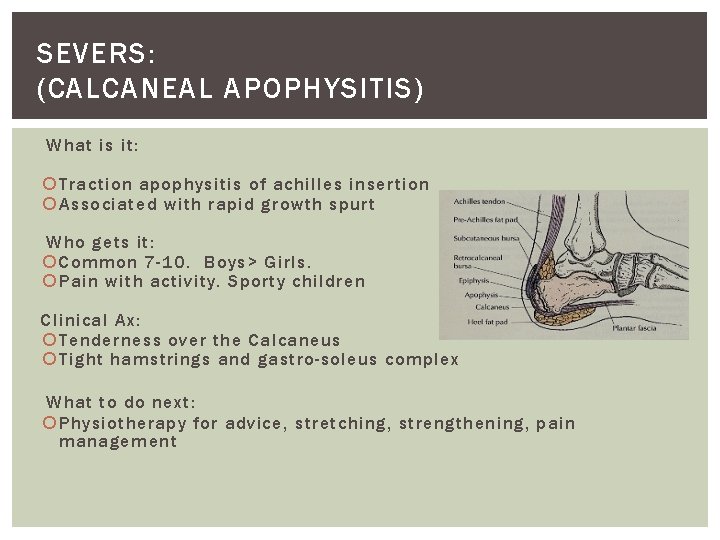

SEVERS: (CALCANEAL APOPHYSITIS) What is it: Traction apophysitis of achilles insertion Associated with rapid growth spurt Who gets it: Common 7 -10. Boys> Girls. Pain with activity. Sporty children Clinical Ax: Tenderness over the Calcaneus Tight hamstrings and gastro-soleus complex What to do next: Physiotherapy for advice, stretching, strengthening, pain management